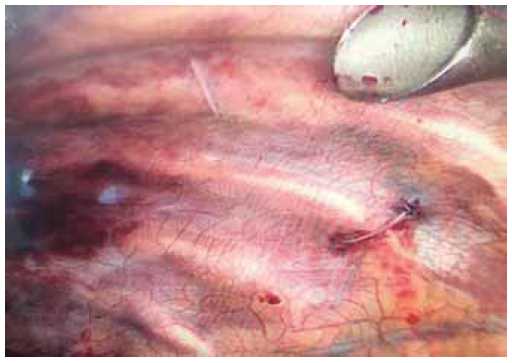

In thoracoscopy, a blood clot with a volume of up to 150 mL was evacuated from the pleural cavity. Further, the right lung was traumatically changed; that is, there was pulmonary contusion. The material for stabilization of the chest frame was the Cramer splint that was V-shaped to increase the contact area with the chest and to mold it in the shape of the chest frame. For fixation, a caprone thread no. 5 with a large cutting needle was used to insert it under the ribs. The procedure was performed in the operating room during video-assisted thoracoscopy under endotracheal anesthesia. After marking the floating area of the chest and processing the surgical field, percutaneous sutures were taken under the ribs with the needle passing along the upper edge of the rib and under the rib in the downward direction; thereafter, the needle was removed through the skin under video-assisted thoracoscopic control (Figure 2).

Fig. 2. View with videotorakoskopii - visible ligatures, carried out from the skin